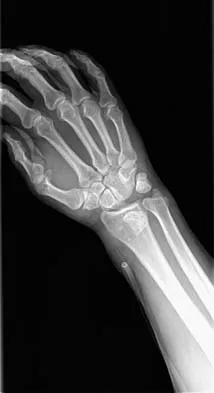

A 32-year-old man has intense right hand and wrist pain, a deformed wrist, and numbness in his fingers after falling off his motorcycle. This is an isolated injury. Examination reveals a swollen wrist, normal capillary refill to all fingers, and limited flexion of all fingers. Radiographs are shown in Figures 21a and 21b. Neurologic examination of the hand will most likely reveal